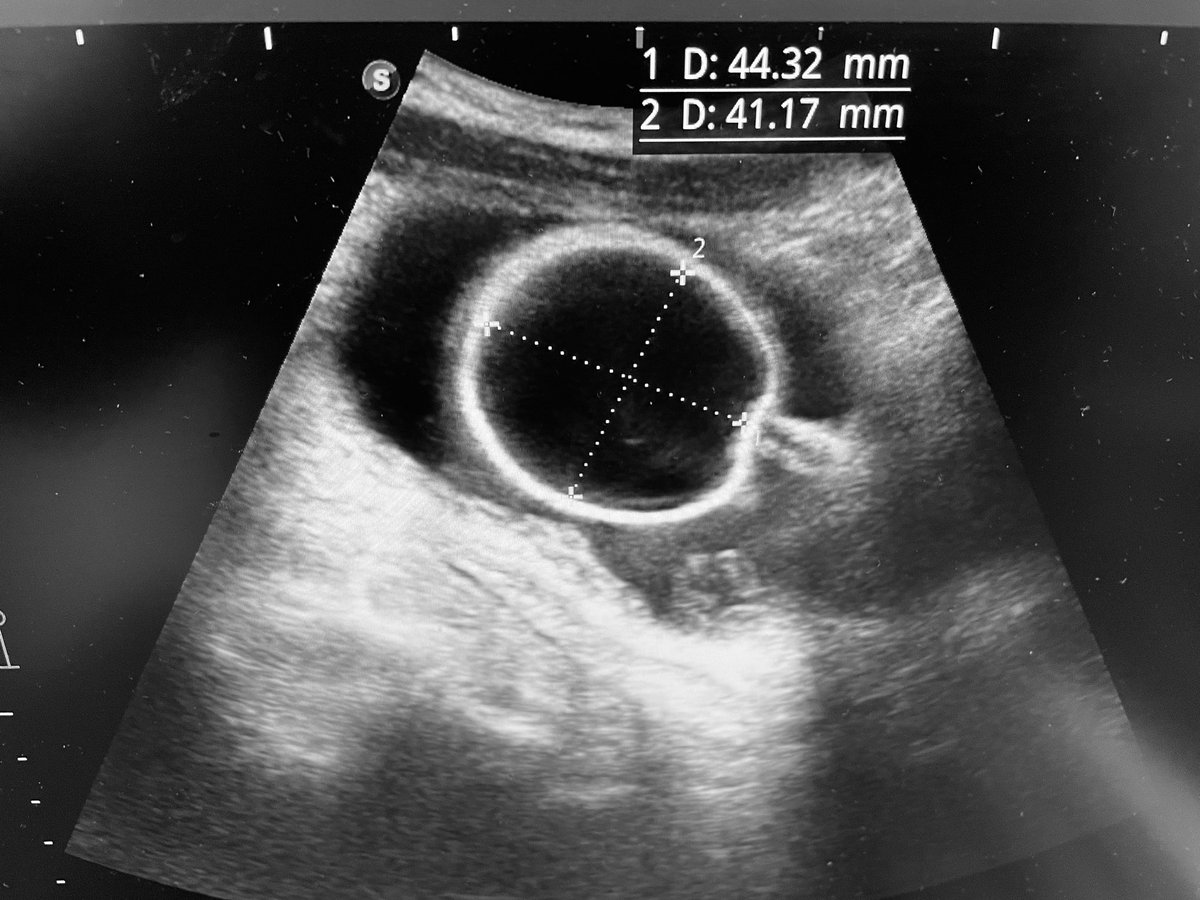

Think you need a CTU to detect duplex system? Not always! Careful US can alert you early and prevent wrong Ureteric catheter insertion — before PCNL, for example. #UroTips @Endo_Sec_Eua @Endo_Society @endouroacademy

Careful US can alert you early and prevent wrong Ureteric catheter insertion — before PCNL, for example. #UroTips @Endo_Sec_Eua @Endo_Society @endouroacademy